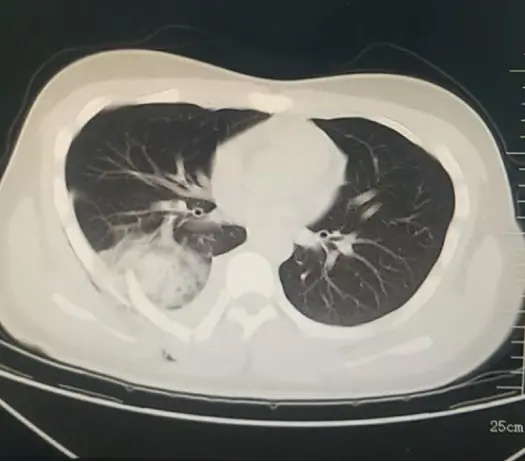

近日,宋先生(化名)因右侧胸痛三月余辗转当地多家医院就诊,检查肺CT示右肺下叶较大占位性病变,由于病灶位于气管外,操作难度较大,多次取材均未成功,为宋先生及家属带来极大困扰。为寻求进一步诊疗,宋先生慕名来到哈医大四院松北院区呼吸内科门诊,才旭副主任详细了解病情后,建议采用超声支气管镜引导下肺占位活检。术前讨论时,才旭副主任提出宋先生右下肺病灶较大,采集标本时如何避开坏死区域,松北院区超声科张立维...